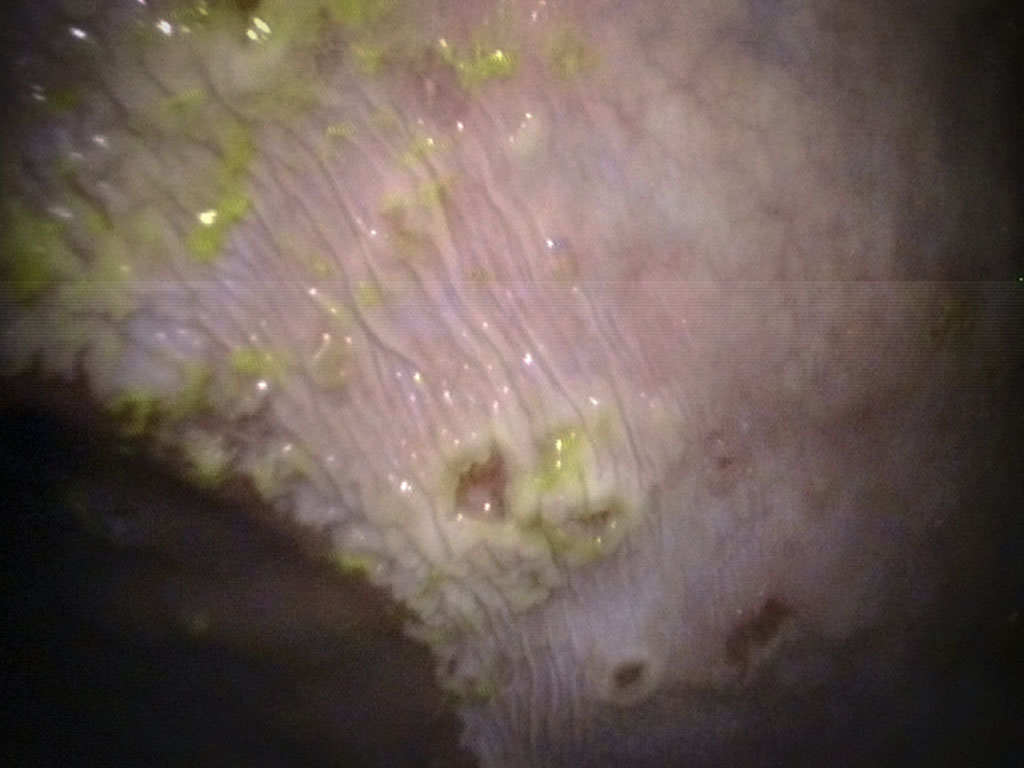

The only way to confirm that your horse has ulcers is to do a Gastroscopy. The procedure is done at a clinic under light sedation. The night before the horse must be held off all feed. This is the most important step as it allows the stomach to completely empty and gives the veterinarian the best chance to visualize the entire stomach lining. Then, under light sedation, the veterinarian will pass a 3 meter endoscope into the nostril, down the esophagus and into the stomach. Once there, we can visualize the gastric mucosa and evaluate it for the presence of ulcers. Repeat gastroscopy may be necessary to insure the ulcers are healing post treatment.